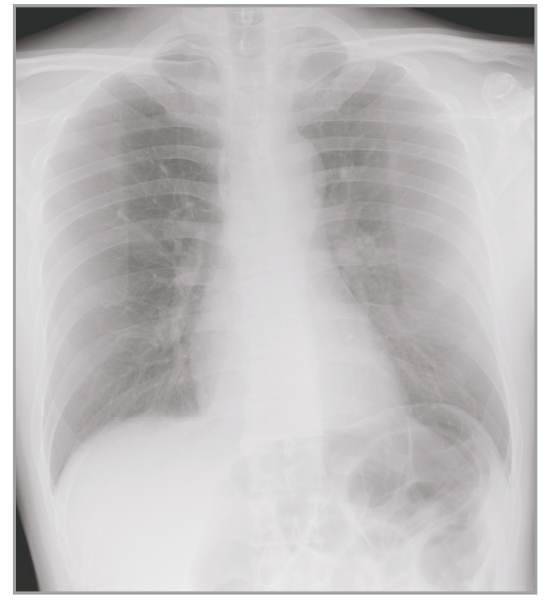

Dynamic Visualization II

Optimizes image quality using latest Exposure Data Recognizer

Advanced recognition algorithms using automatic  calculations of estimated 3D image data, identify the body part required and adjusts contrast, density and enhancement for optimised image display. (Option)

Comparison of Dynamic Visualization II vs. conventional processing images (Lumbar Spine)

Comparison of Dynamic Visualization II vs. conventional processing images (Hip Joint)